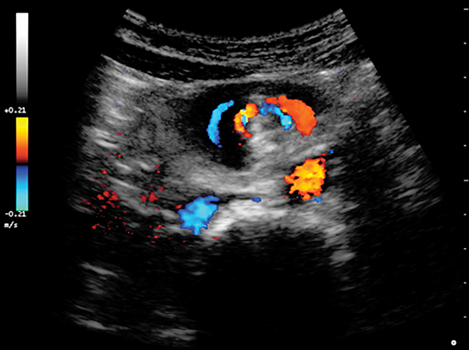

Paciente de sexo femenino, de 18 años, que concurre al servicio de emergencias presentando dolor epigástrico agudo e intermitente de 6 horas de evolución. Semiológicamente el dolor empeora con la ingesta y se asocia con náuseas y vómitos de tipo biliosos. Al examen físico, llama la atención la marcada distensión abdominal. Se solicitan como estudios complementarios una ecografía abdominal (Figura 1), un tránsito de intestino delgado con contraste hidrosoluble (Figura 2) y una tomografía computada con contraste oral y endovenoso (Figura 3).